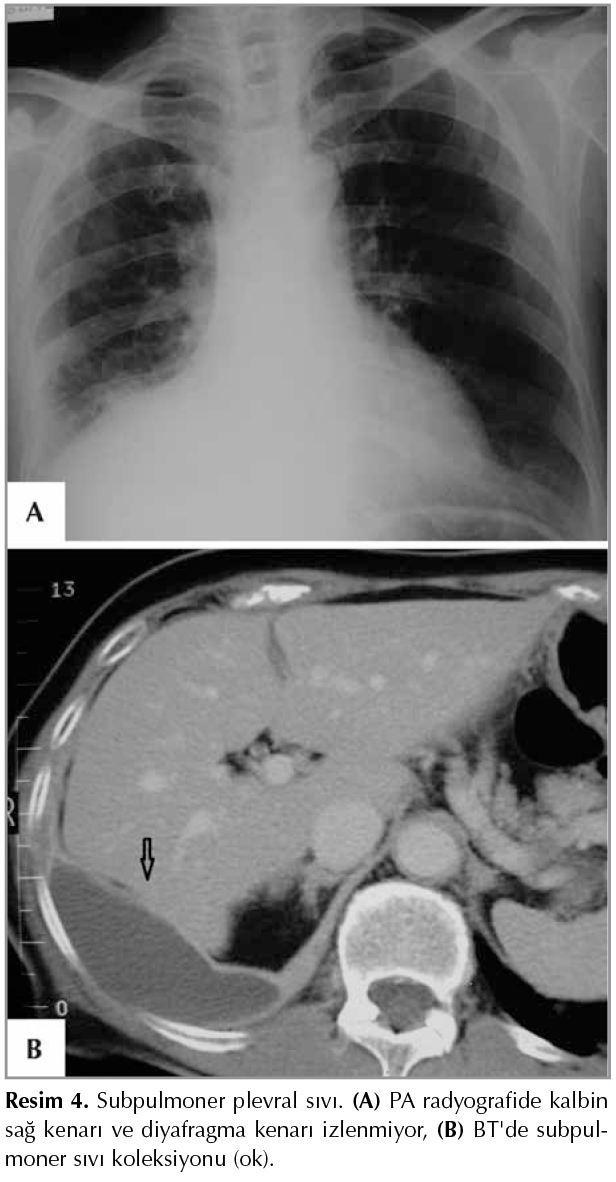

Tuberkuloz Ve Toraks Plevral Hastaliklarin Goruntulenmesi Akciger Grafisi Temelinde Goruntuleme Yontemlerinin Degerlendirilmesi